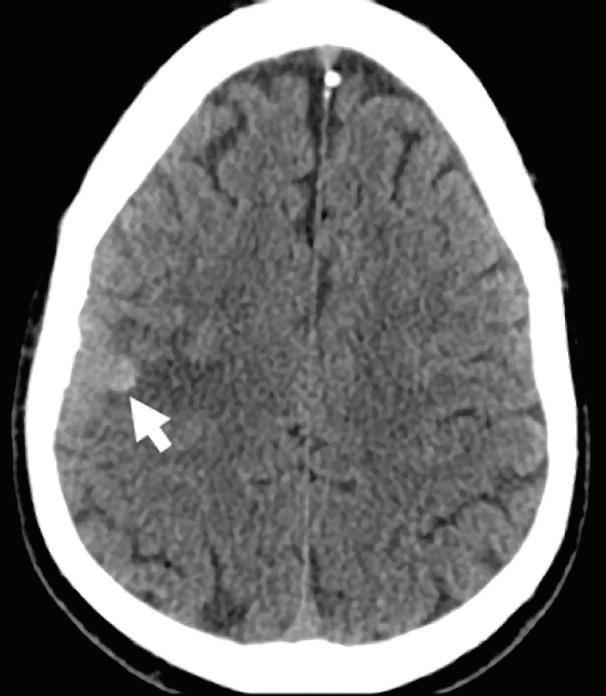

33-year-old testicular carcinoma patient with previously resected brain metastasis presented with seizures.

Axial images

Conventional non-contrast CT scan showed an area of hemorrhage on the right parietal lobe. A small portion showed contrast enhancement on lateral aspect of the lesion. Virtual non-contrast images were comparable to true non-contrast images. Iodine density and Z effective images showed iodine uptake indicating a metastatic foci with hemorrhagic component. The mass was resected and metastasis was confirmed at pathology.

Discussion

Contrast uptake could be masked by hyperdense hemorrhage in a hemorrhagic mass lesion on conventional CT images. Iodine density and Z effective images are useful to identify the presence of iodine in the lesion, and allowing therefore a more confident diagnosis of an underlying mass. Virtual non-contrast images are comparable to true non-contrast images. A reduction of radiation dose to the patient is possible by omitting true non-contrast images.

Conventional CT non-contrast axial image: hyperdense area of hemorrhage (arrow).

Virtual non-contrast axial image: hyperdense area of hemorrhage (arrow).

Conventional CT axial image with contrast: enhancement of the lateral aspect of the mass (arrow), difficult to differentiate from the hemorrhagic background.

Iodine density image: iodine uptake of the lateral portion of the lesion; iodine concentration of the mass (1.93 mg/ml, blue arrow) is higher compared to adjacent brain parenchyma (1.00 mg/ml, white arrow).

Z effective image: effective atomic number of the lateral portion of the mass is higher (8.70, blue arrow) compared to adjacent brain parenchyma (8.03, white arrow), indicating iodine uptake of the lesion.